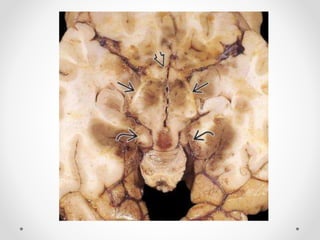

Xuất huyết Duret

- Là một hoặc nhiều ổ xuất huyết nhỏ ở cầu và hành não, sau

thoát vị qua lều hướng xuống, đặc biệt là thoát vị trung tâm.

Thường thấy ở BN có thoát vị trung tâm mức độ nặng từ 12-

24h trước khi chết

 Hình ảnh điển hình: một ổ xuất huyết tròn, nhỏ nằm ở đường

giữa hành não hoặc cầu não vị trí nối với cuống não.

 Chẩn đoán phân biệt:

- Xuất huyết do tăng huyết áp nguyên phát: thường lớn hơn,

nằm ở phần giữa cầu não, không có thoát vị não

- Dập não/ tổn thương sợi trục lan toả: ở mặt lưng của thân não(

quanh cống não và mảnh sinh tư), thường đa ổ và kích thước

nhỏ hơn

Xuất huyết Duret -Là một hoặc nhiều ổ xuất huyết nhỏ ở cầu và hành não, sau thoát vị qua lều hướng xuống, đặc biệt là thoát vị trung tâm. Thường thấy ở BN có thoát vị trung tâm mức độ nặng từ 12- 24h trước khi chết  Hình ảnh điển hình: một ổ xuất huyết tròn, nhỏ nằm ở đường giữa hành não hoặc cầu não vị trí nối với cuống não.  Chẩn đoán phân biệt: - Xuất huyết do tăng huyết áp nguyên phát: thường lớn hơn, nằm ở phần giữa cầu não, không có thoát vị não - Dập não/ tổn thương sợi trục lan toả: ở mặt lưng của thân não( quanh cống não và mảnh sinh tư), thường đa ổ và kích thước nhỏ hơn